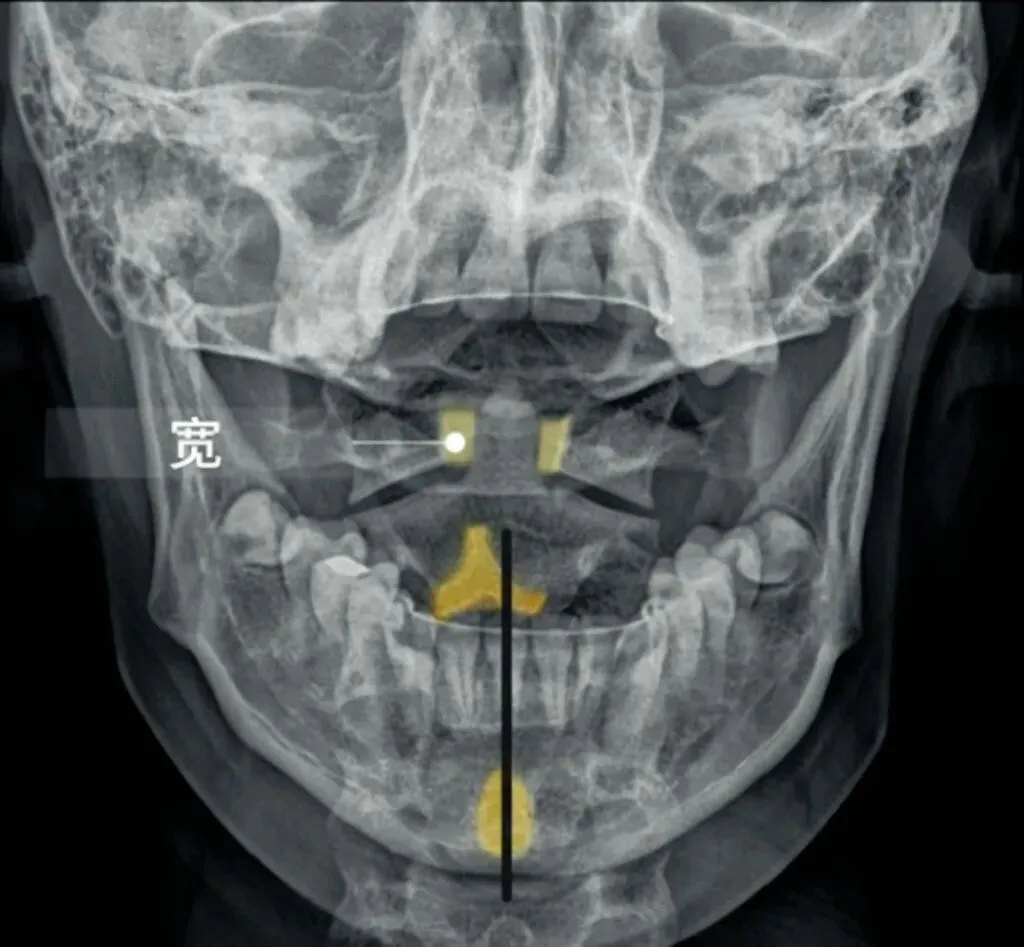

十张口是指寰枢椎的结构和位置关系,我们主要观察寰齿间隙和寰枢关节间隙及寰椎侧块的大小,来判断寰枢关节有无脱位的情况。

首先是寰齿间隙,如果枢椎与颈三的棘突位于同一条直线,

那么寰齿间隙哪边宽,就代表寰椎向哪边发生了侧方移位。

如果不在一条直线上,那就代表枢椎也有侧向的移动或旋转。

接下来是寰枢关节间隙,也称寰枢外侧关节,主要看两侧间隙是否等大,

如果一边宽一边窄,就代表寰椎向窄的一方发生了侧向倾斜。

再下来看寰椎侧块的大小,正常情况下侧块两边的宽度是等大的,

如果哪边侧块变大,就代表哪边的侧块向前方发生了旋转。